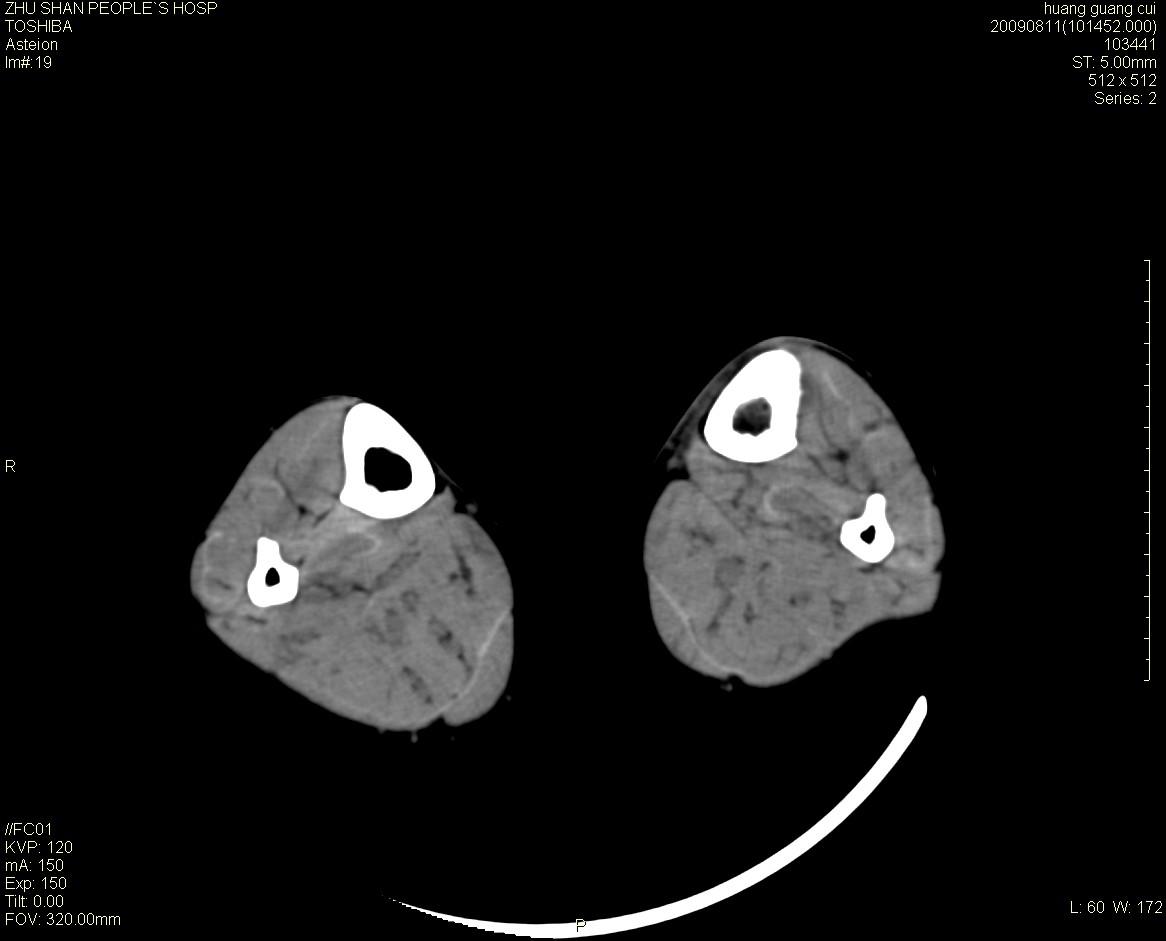

女性 56岁 左胫骨中断肿痛2月余。转移瘤or尤文氏肉瘤?

左侧胫骨中段骨皮质溶骨性破坏,髓腔内外见软组织肿块,无明显钙化及成骨,定位相显示病变周围“筛孔样”改变,定性恶性无疑,原发或转移均有可能,倾向于骨纤维肉瘤可能性大,转移瘤不排除。膝关节以下骨转移很少,且要有原发灶支持,尤文氏肉瘤年龄太大不支持。